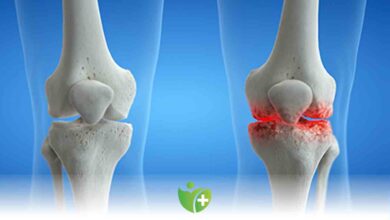

Yüksek tibial osteotomi

Diz Kireçlenmesi sorunu yaşıyorsanız

Genç veya orta yaşlı bireylerde halk arasında diz kireçlenmesi olarak bilinen sorunu tedavi etmek için yapılan ve kemik düzeltici cerrahi…